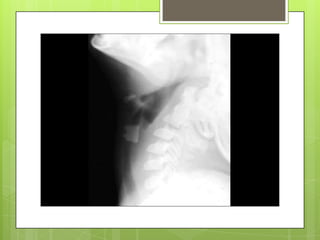

 Roentgenographic

examination.

or fluoroscopic